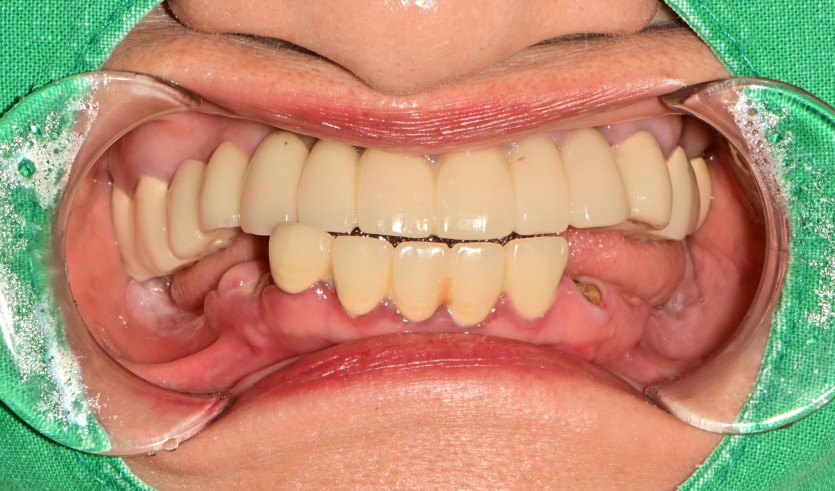

만 59세 전체 임플란트 증례

전체 임플란트 증례입니다.

16개의 임플란트로 완성하였습니다.